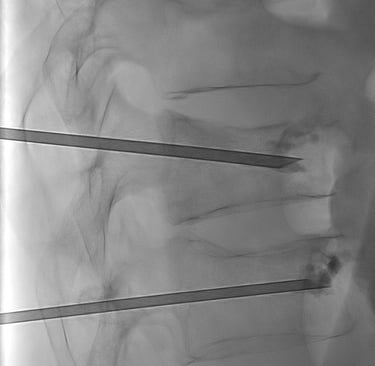

A l’aide d'un guidage radiologique par radiographie ou scanner, le médecin Radiologue Interventionnel va positionner une aiguille de vertébroplastie à travers la peau directement au sein de la vertèbre à traiter.

Le ciment est en suite injecté à travers l'aiguille jusqu'au bon remplissage de la vertèbre. L'injection est surveillée par les images de radiographie pour éviter les fuites de ciment.

Cimentoplastie percutanée réalisée dans notre centre : Photo 1 : aiguilles en place dans chaque vertèbre fracturée. Photo 2 : injection du ciment visible en radiographie (têtes de flèches bleues).